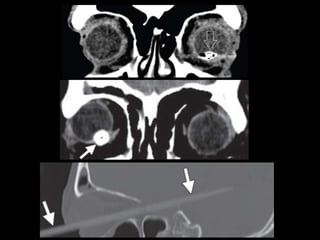

TC

Rotura ocular

• Rotura de la esclera

• Sensibilidad del 56%–68%

– Signos directos:

• Alteración del contorno o volumen (múltiples planos)

• Discontinuidad esclera

– Signos indirectos

• Aumento de profundidad de la cámara anterior

• Aire o cuerpo extraño intraocular

• Mimics

Cuerpos extraños

• Inorgánicos: metal, cristal (sensibilidad 50% en

< 0.5 mm) y plástico. Sin inflamación

• Orgánicos: Madera (densidad similar al aire

pero con forma geométrica) va aumentando

de densidad con el tiempo. RM!

• RM contraindicada en metálicos (más sensible

en orgánicos)

Rotura ocular • Roturade la esclera • Sensibilidad del 56%–68% – Signos directos: • Alteración del contorno o volumen (múltiples planos) • Discontinuidad esclera – Signos indirectos • Aumento de profundidad de la cámara anterior • Aire o cuerpo extraño intraocular • Mimics

Cuerpos extraños • Inorgánicos:metal, cristal (sensibilidad 50% en < 0.5 mm) y plástico. Sin inflamación • Orgánicos: Madera (densidad similar al aire pero con forma geométrica) va aumentando de densidad con el tiempo. RM! • RM contraindicada en metálicos (más sensible en orgánicos)